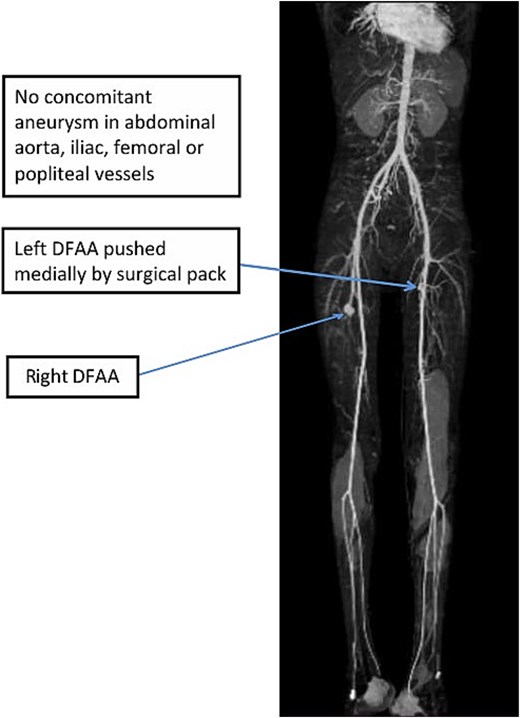

White blood cell count was 13,700 and hemoglobin was 3.4 mg/dl. CTA revealed bilateral DFAAs with the left measuring a maximal diameter of 9.32 mm with adjacent surgical pack pushing the vessels medially and a right concentric unruptured DFAA measuring 2.05 cm (Figs 1–3).

3D-maximum intensity projection frontal view of lower limb CTA showing bilateral DFAA.